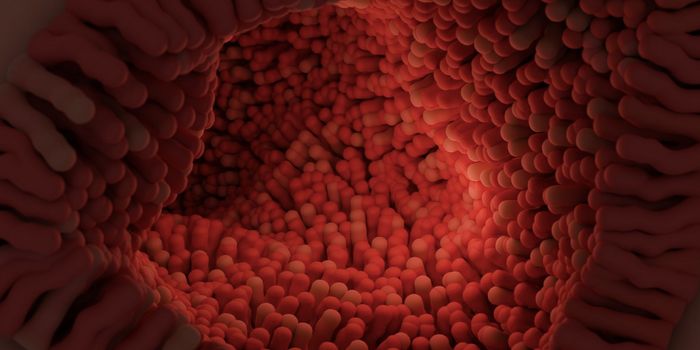

SEP 08, 2024Cell & Molecular BiologyThe human small intestine is an essential organ that helps us absorb nutrients and vitamins from food. It is an average ...